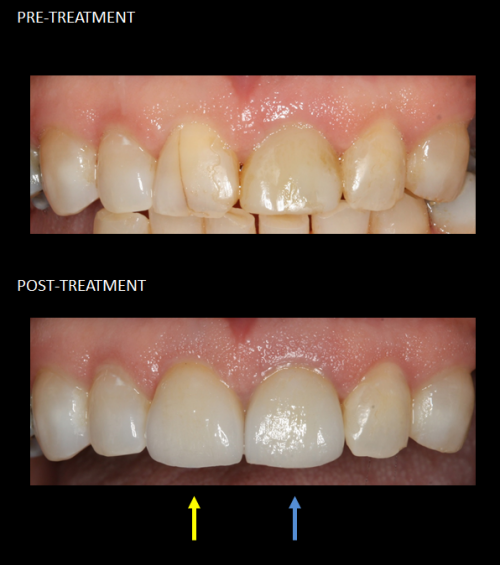

Restoration of front teeth with a same-day implant (blue) and matching crown (yellow).